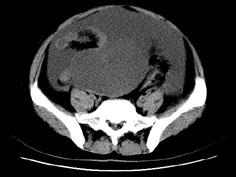

问题 女,27岁,腹胀伴消瘦两个月,CT检查如图所示,应诊断为 ( )

选项 A、卵巢粘液性囊腺瘤 B、卵巢粘液性囊腺癌 C、卵巢浆液性囊腺瘤 D、卵巢浆液性囊腺癌 E、子宫肌瘤

答案 D